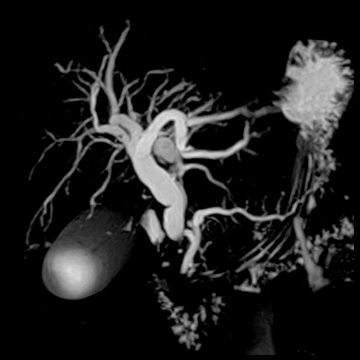

頭部MRA

腫瘍

matrix 320, FOV 220 mm- 頭部MRA